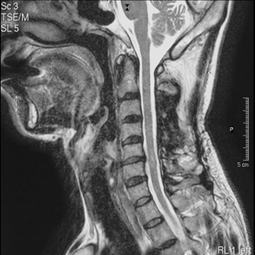

臨床応用例 |